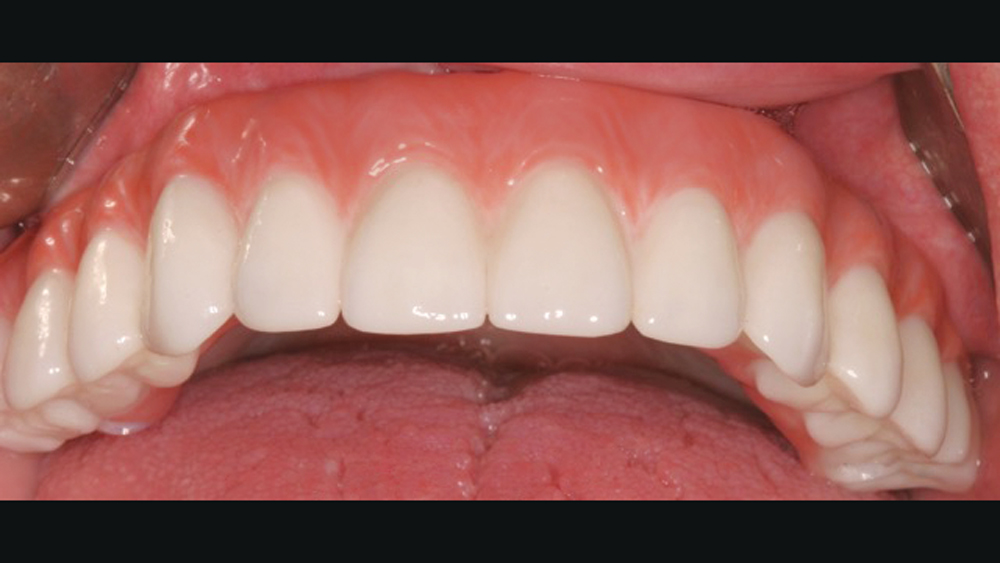

Once osseointegration is complete, the BruxZir® Full-Arch Implant Prosthesis is the ideal choice for the restoration, as its monolithic construction prevents chips, stains, breakage, and dislodged or worn-down prosthetic teeth.3,4 This treatment option has helped elevate the quality of care I’m able to provide for my edentulous patients, who no longer return to my office with a broken acrylic appliance in hand.

The following case demonstrates how to immediately place implants in full-arch indications. By properly positioning the implants, maximizing primary stability and providing the most durable restoration possible, the short- and long-term needs of the patient are addressed in an efficient, predictable manner.

For patients with adequate quantity and quality of bone, extraction with immediate implant placement is an efficient means of tooth replacement that reduces the number of surgical procedures and shortens the duration of treatment. In full-arch indications, this approach can deliver results that instantly transform dental form, function, personal confidence and quality of life. Achieving a predictable, long-lasting result has been simplified by innovations in implant design and prosthetics, making this an excellent option for practitioners providing implant therapy for their terminal dentition or edentulous patients.